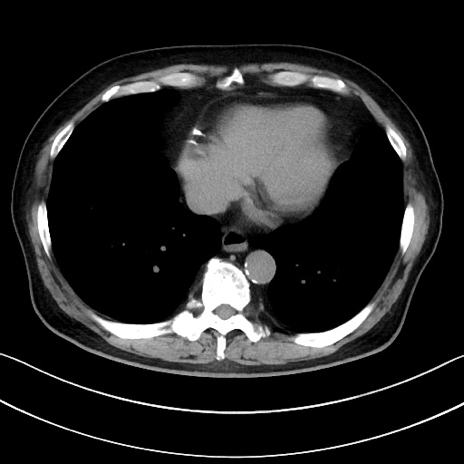

冠状断像

【症例】70歳代男性

【主訴】腹痛

【現病歴】今朝から腹痛あり。全体的に痛い。特に左上の方。排ガスが今日はない。冷や汗が出る。

【既往歴】直腸癌術後

【身体所見】左側腹部〜上腹部に圧痛あり。腹膜刺激症状明らかなではない。軽度反跳痛。左下腹部に術後瘢痕あり。

【データ】WBC 7700、CRP 0.02